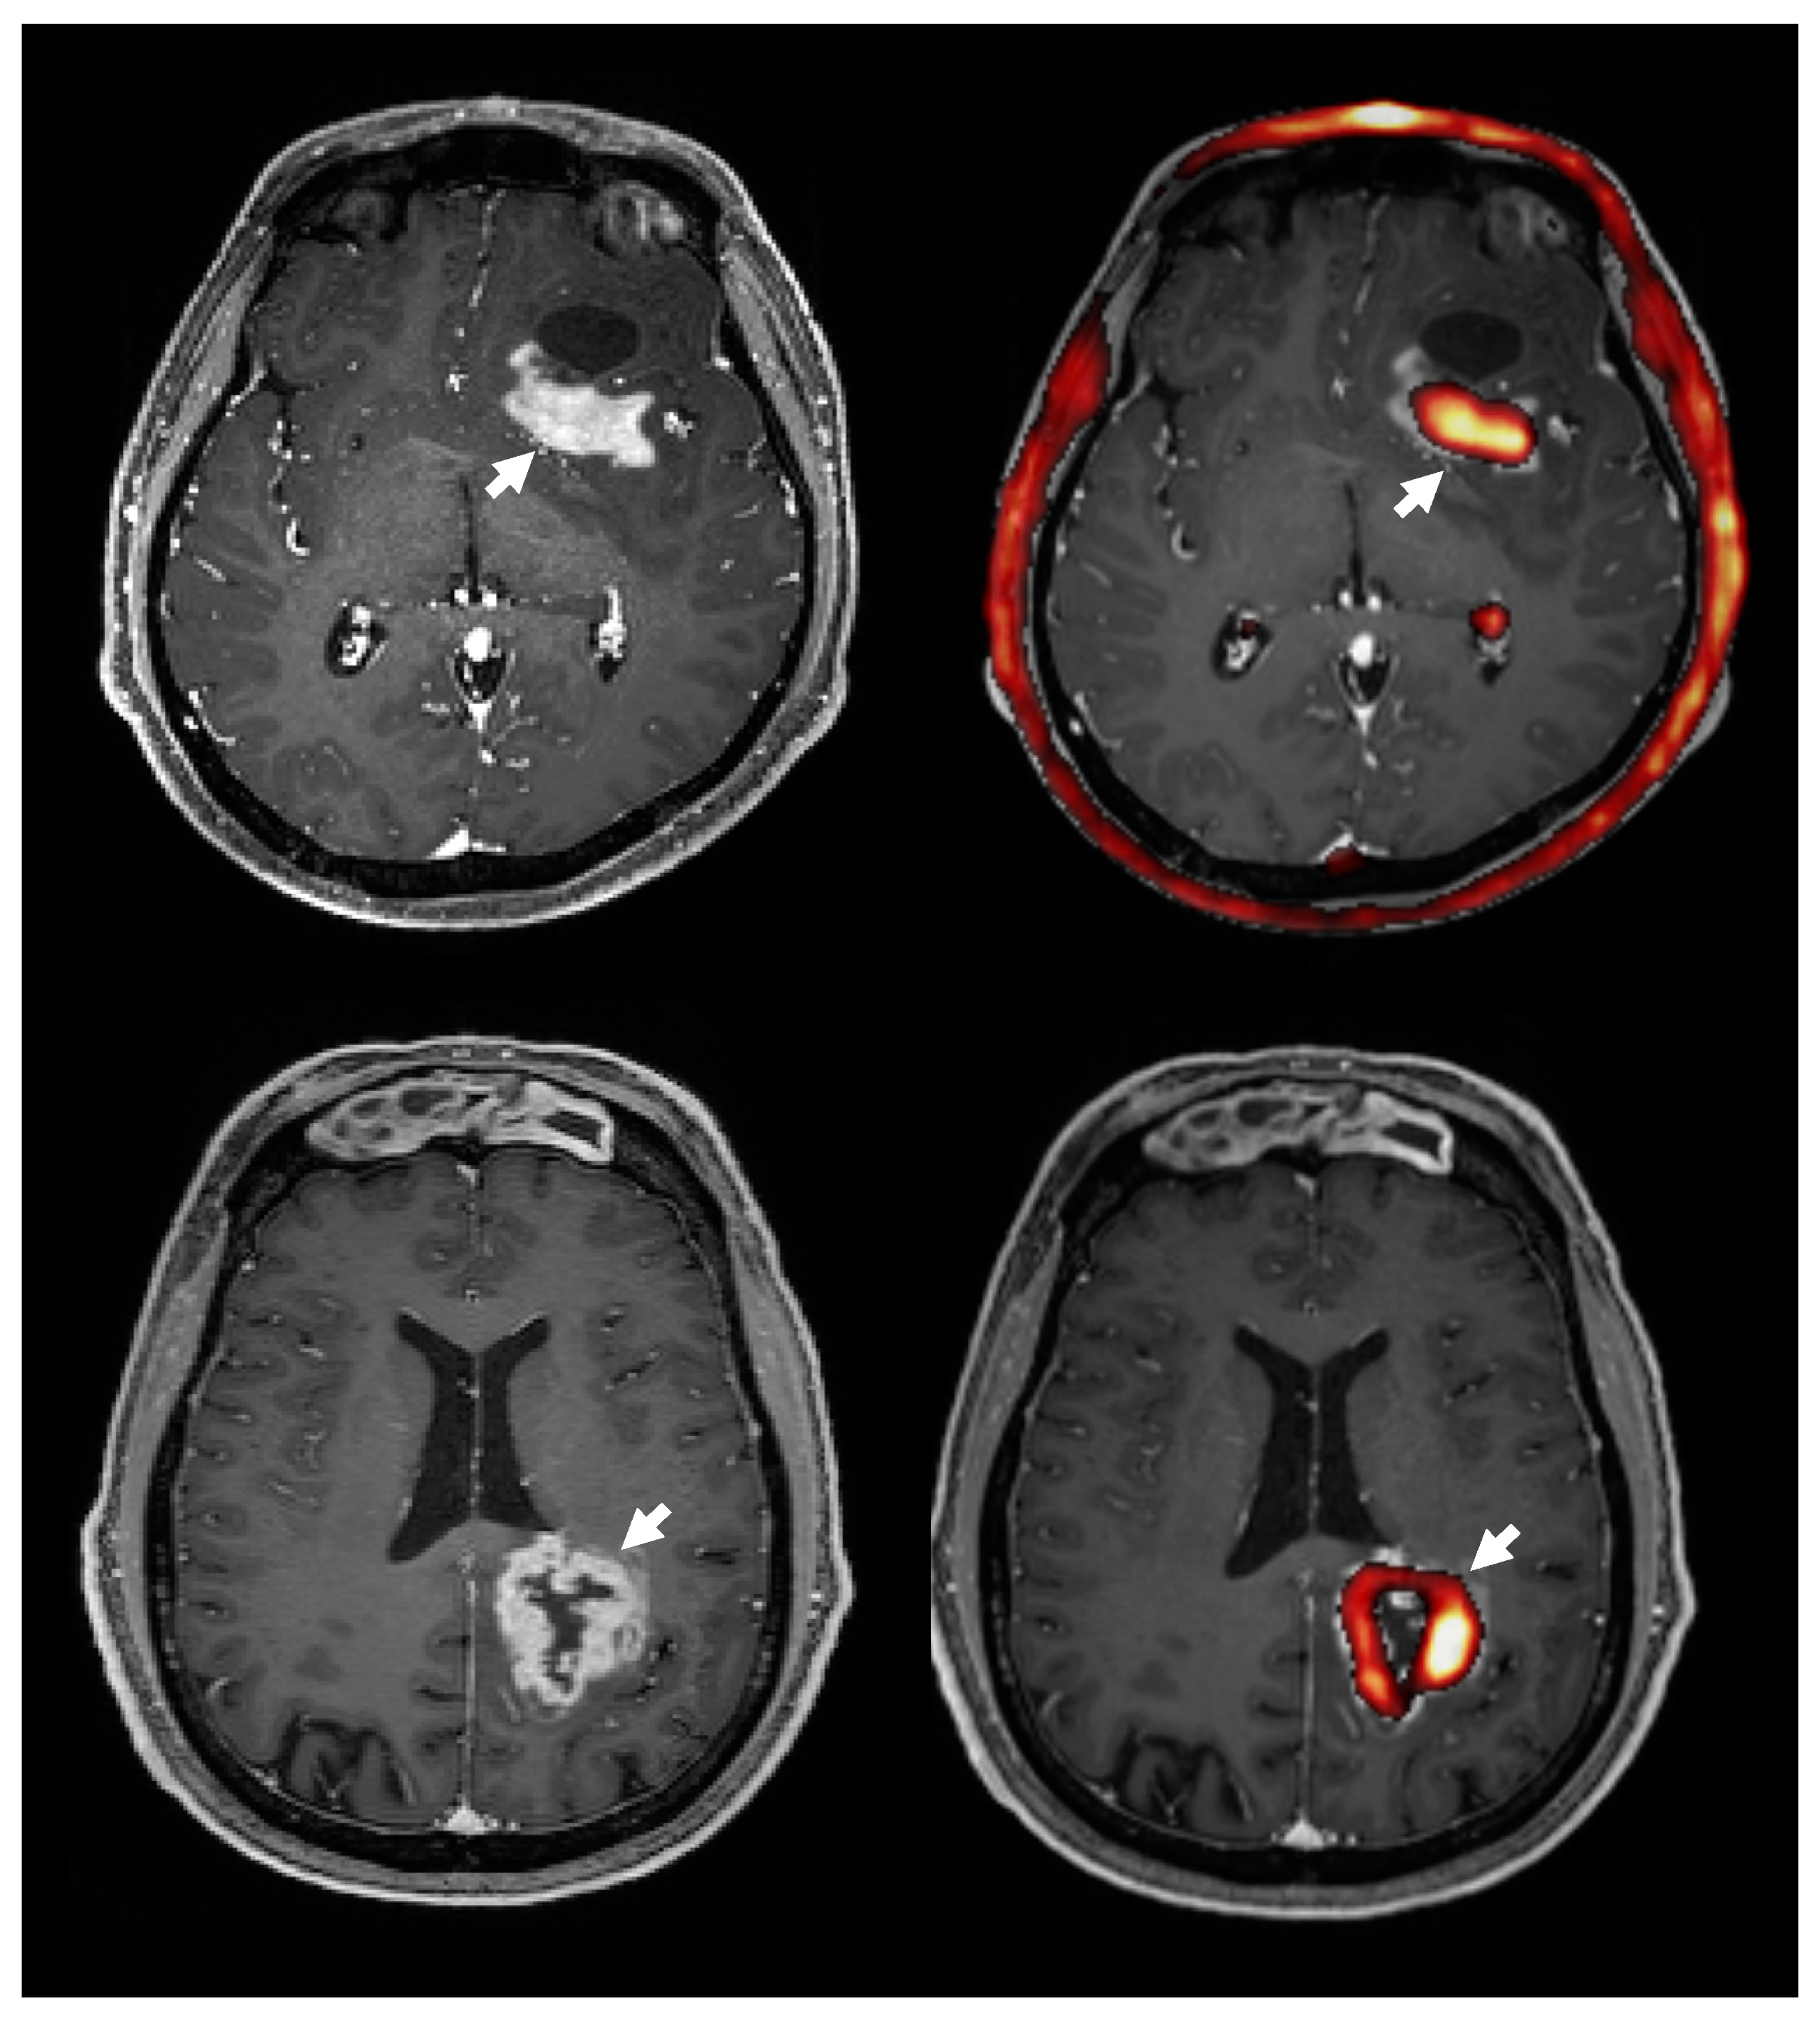

3.8. Choline PET Uptake vs. Contrast Enhanced T1 MRI

4.4. 18F-FMC PET vs. MRS